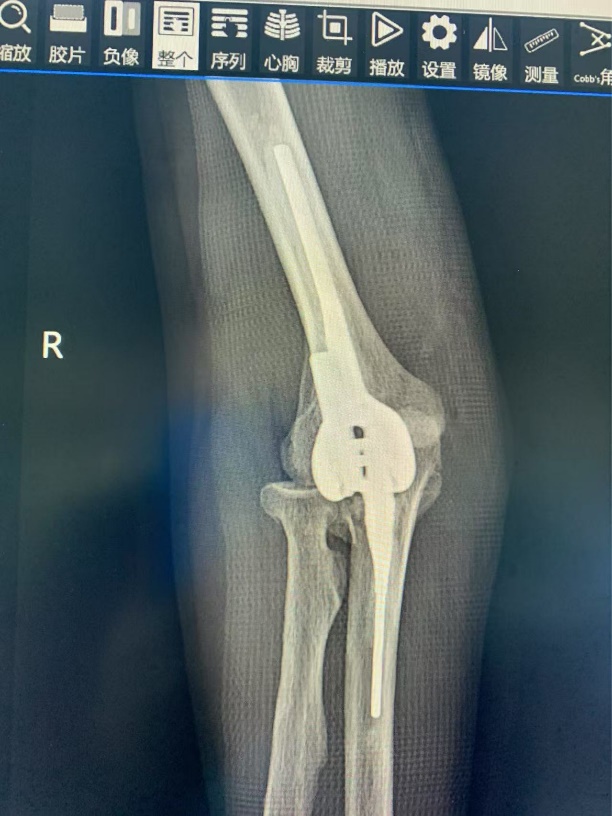

术后复查肘关节 X 片

湘南学院附属医院骨一科团队在了解李师傅的艰难处境后,迅速行动。经过全面细致的检查和专业评估,团队制定了精准的手术方案 ——为李师傅实施人工肘关节置换术及尺神经松解术。手术由经验丰富的唐新文主任主刀,郭志文副主任医师、刘红粘主治医师等紧密配合。术中,团队凭借娴熟的技术和高度专注,确保了手术顺利进行。术后,在医护人员精心照料下,李师傅恢复良好,肘关节活动能力大幅改善,感觉麻木、手指无力、肌肉萎缩等尺神经症状也完全消失。